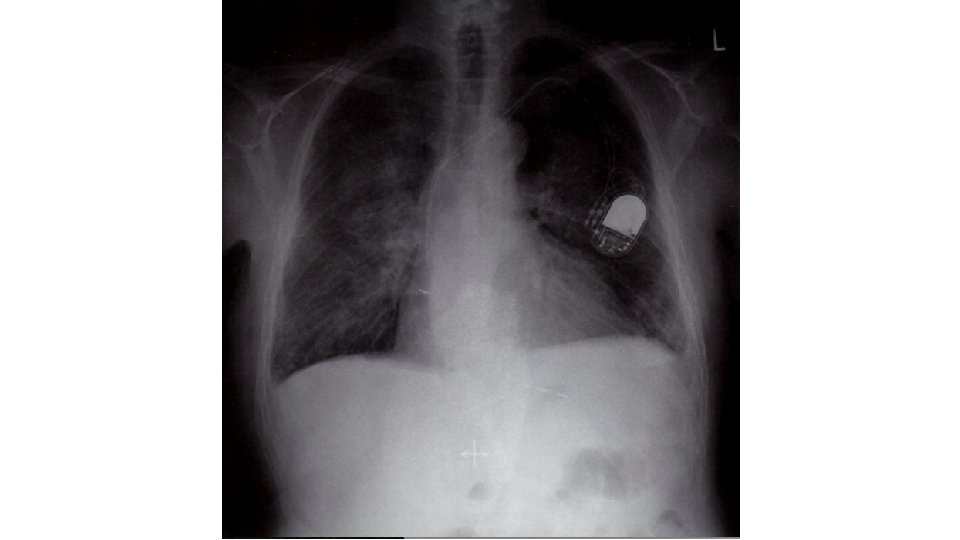

PRUEBAS COMPLEMENTARIAS Pruebas de imagen: Ecografía cardíaca, pulmonar RX tórax § ECG Biomarcadores: Analítica: Ca 125 Creatinina/urea Na/K en sangre y orina Hb (> 10. 5 no se trata) Albúmina Gasometría: - p. H - Hipoxemia/normocapnia NT-pro. BNP